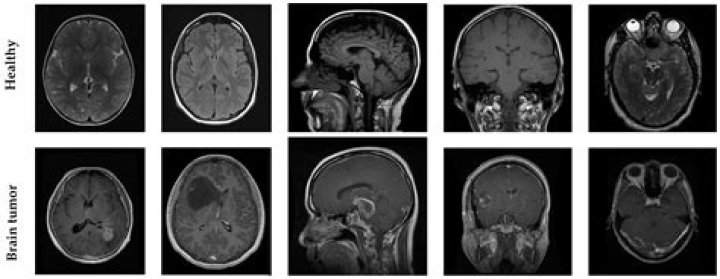

Loss of volume of the part of the Brain Results of several MRI scan studies have demonstrated people with depression had a hippocampus volume that was up ...